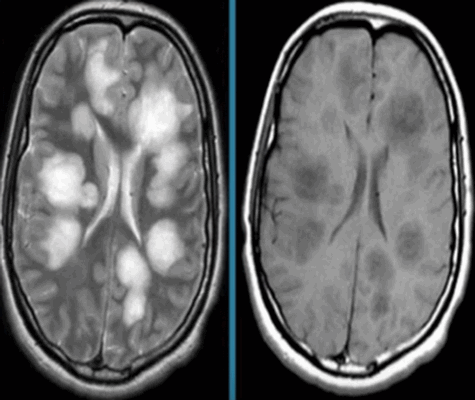

Картина развития ишемического инсульта на МРТ (Т1- и Т2-взвешенные изображения)

Острый период (1-7 день) характеризуется появлением четко ограниченных светлых участков на МРТ в Т2-взвешенном режиме. На Т1 ВИ очаги некроза имеют гипоинтенсивный сигнал.

Головной мозг на МРТ при разных режимах сканирования

Для заболевания характерно появление очагов некроза, вызванного нарушением кровоснабжения определенного участка мозга. В острой стадии наблюдается утолщение извилин коры головного мозга, стирается граница между серым и белым веществом. В период восстановления зону инфаркта определяют как участок кистозного или глиозного перерождения.